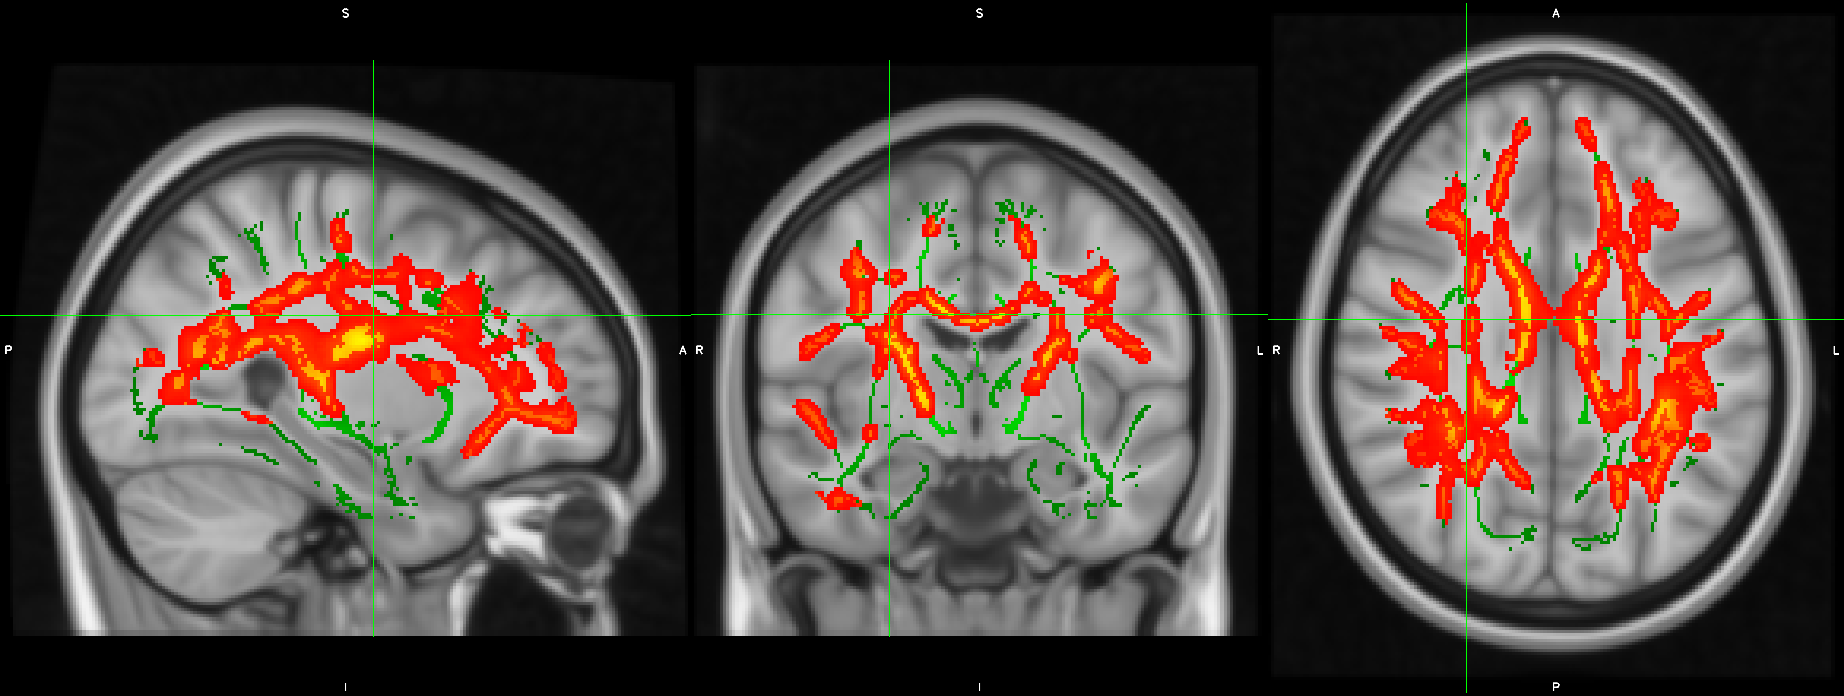

Un nou estudi publicat per l’Institut de Recerca de l’Hospital del Mar alerta que el consum de cànnabis pot suposar un problema greu en els tractaments antipsicòtics. Els investigadors assenyalen que consumir cànnabis està associat amb un increment de la inflamació cerebral, un fet que podria interferir en la capacitat terapèutica dels tractaments antipsicòtics. “Les persones que pateixen un primer episodi psicòtic i consumeixen cànnabis presenten més inflamació cerebral que aquelles que pateixen el mateix trastorn, però no consumeixen aquesta substància. Un efecte que és el contrari del que passa en el cas de les persones sanes”, assenyalen els investigadors.

En l’estudi hi han participat 62 pacients diagnosticats de forma recent i 38 controls. Els investigadors destaquen que es mostren diferències en la inflamació cerebral entre aquelles persones pateixen un primer episodi psicòtic i que consumeixen cànnabis o no. Els autors de l’estudi destaquen que aquestes diferències “també es veuen en les persones que no tenen psicosi, encara que consumeixin”. El doctor Daniel Bergé, psiquiatre de l’Hospital del Mar i membre del Grup de Recerca en Neuroimatge en Trastorns Mentals de l’Hospital del Mar Research Institute, assenyala que l‘estudi “suggereix una associació entre l’ús de cànnabis i alteracions en el sistema inflamatori en els primers episodis psicòtics”. Bergé afegeix que “la potencial associació del consum d’aquesta substància amb l’alteració de la reducció de la inflamació cerebral assolida gràcies als tractaments antipsicòtics ens ofereix una visió d’un dels possibles factors que influeixen en el baix èxit del tractament en aquests pacients”.